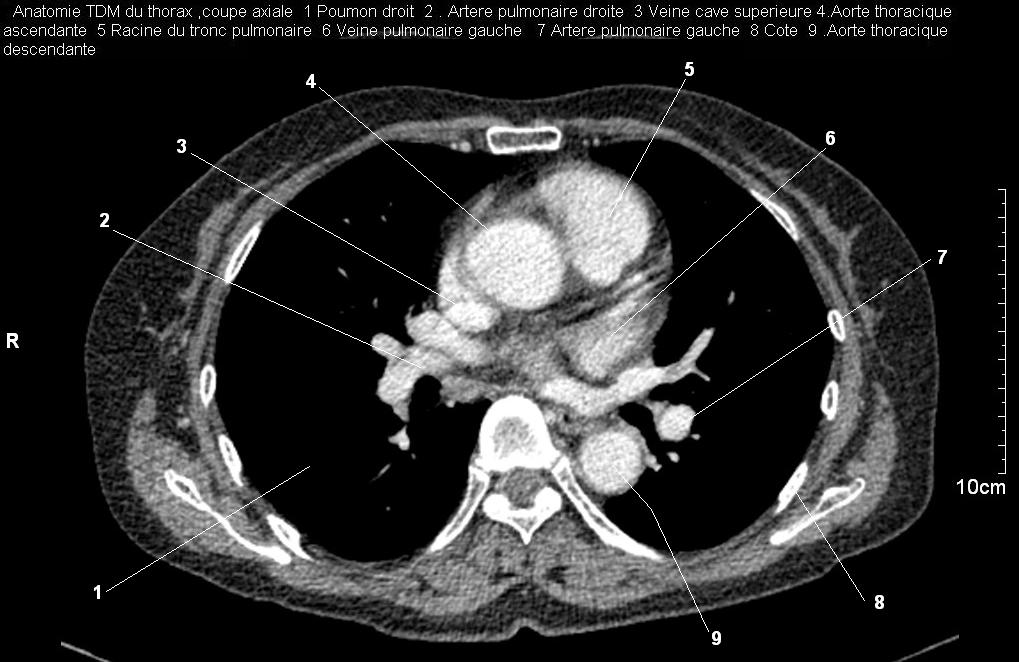

Radioanatomie pulmonaire ( image radiologie thoracique normale )- La Tomodensitometrie du  thorax ( coupes axiales fenetre mediastinale )

Les fenetres mediastinales permettre d'etudier anatomie du mediastin et les structures vasculaires en coupes axiales de 0,5-1cm sur le thorax . Et si elles sont opacifiees par produit de contrast elles sera se donnent des resutats suivantes :